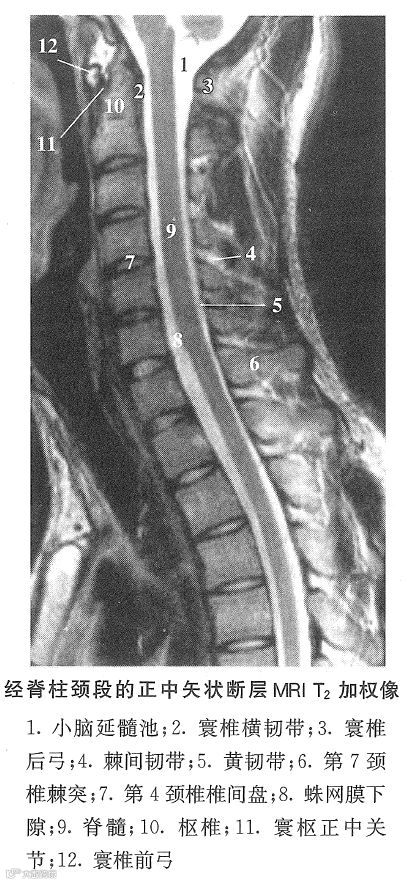

二、颈椎正中矢状断层

脊柱颈曲前凸,顶点在第4~6颈椎平面。寰椎前、后弓断面为圆形。枢椎齿突与寰椎前弓和寰椎横韧带构成寰枢正中关节。颈椎体呈长方形,自上而下逐渐增大。椎间盘连结相邻颈椎体的上、下面。椎间盘的前高大于后高,约为2~3:1,与相邻椎体的高度比约为1:2~4。前纵韧带连于椎体和椎间盘的前面;后纵韧带与硬脊膜相贴,与椎体连结疏松,其间隔有椎体后静脉。

椎管和脊椎的弯曲与脊柱颈曲一致。脊髓位于硬膜囊中央,上端在枕骨大孔处连延髓。蛛网膜下隙位于脊髓的前、后方。硬膜外隙前部有椎内前静脉丛,后部有少量脂肪。

枢椎棘突较粗,第7颈椎棘突长而厚,其余颈椎棘突短,斜向后下。棘间韧带连结相邻棘突。项韧带位于棘突后方。黄韧带较薄,连接相邻椎弓板。